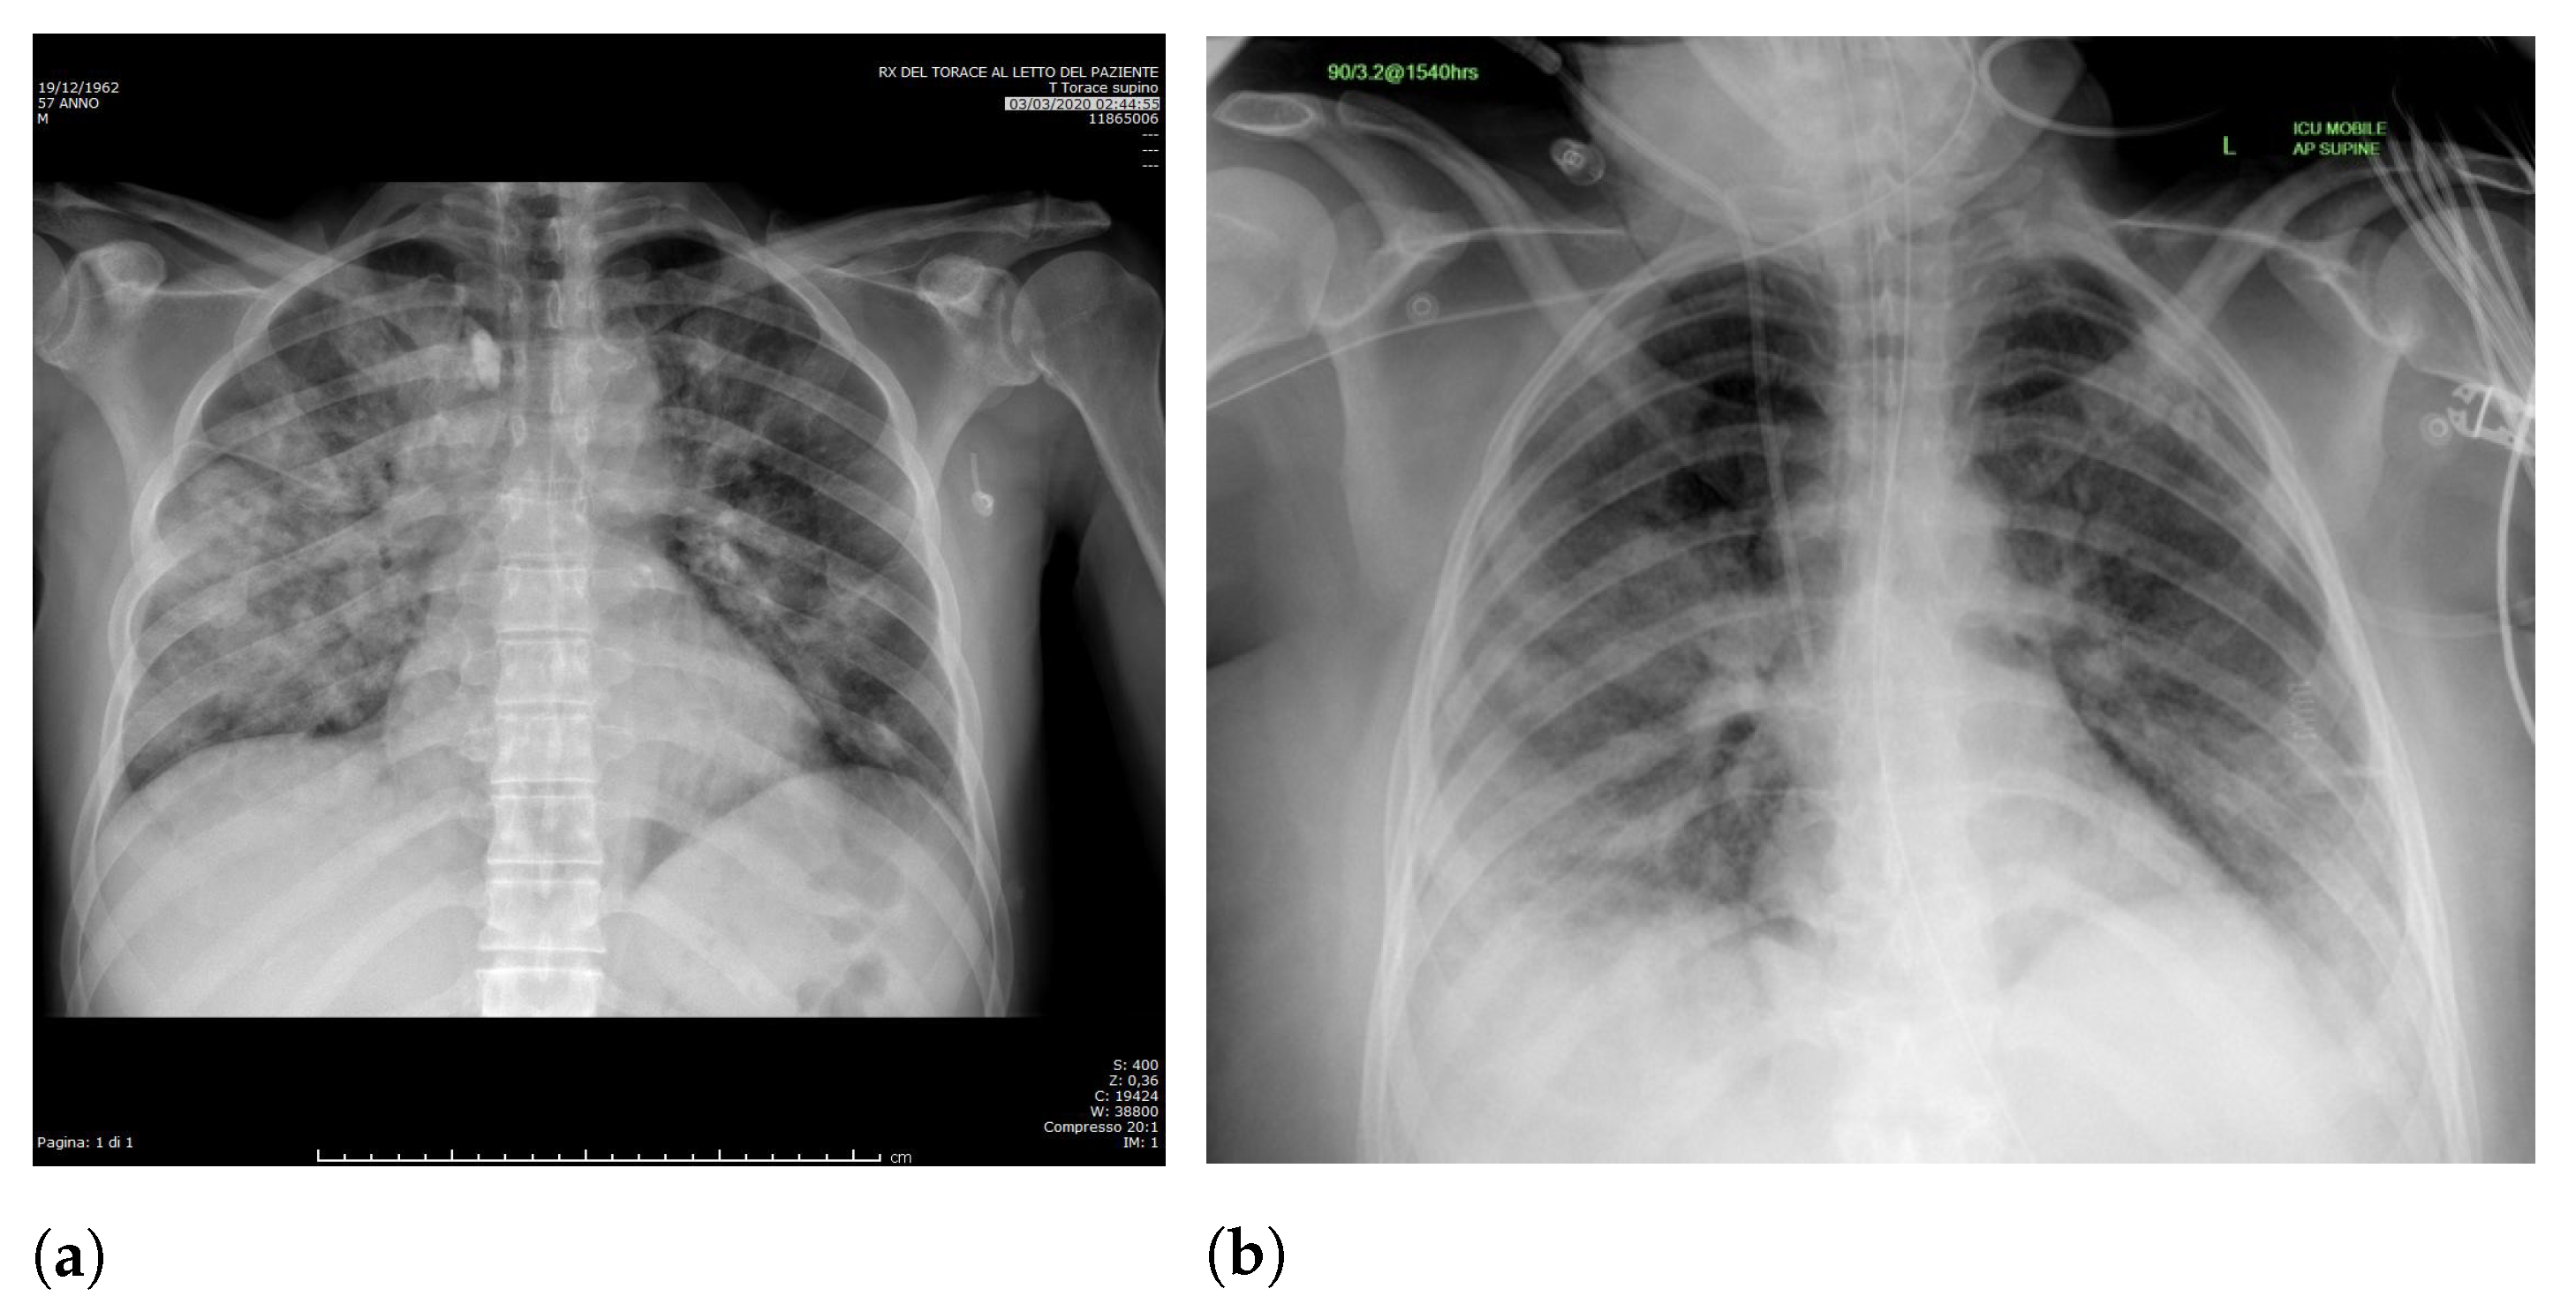

Specifically, in deep models, any extra information can lead to model overfitting. This is especially important in CXR since many images contain burned-in annotations about the machine, operator, hospital, or patient.

Figure 3 presents an example of CXR images with burned-in information.

The most affected class by lung segmentation is the COVID-19, followed by Lung opacity. The Normal class had a minimal impact. The best F1-Scores for COVID-19 and Lung opacity using full CXR images are 0.94 and 0.91, respectively, and after the segmentation, they are 0.83 and 0.89, respectively. We conjecture that such impact comes from the fact that many CXR images are from patients with severe clinical conditions who cannot walk or stand. Thus the medical practitioners must use a portable X-ray machine that produces images with the “AP Portable” annotation and that some models might be focusing on the burned-in annotation as a shortcut for the classification. That impact also means that the classification models had trouble identifying COVID-19.